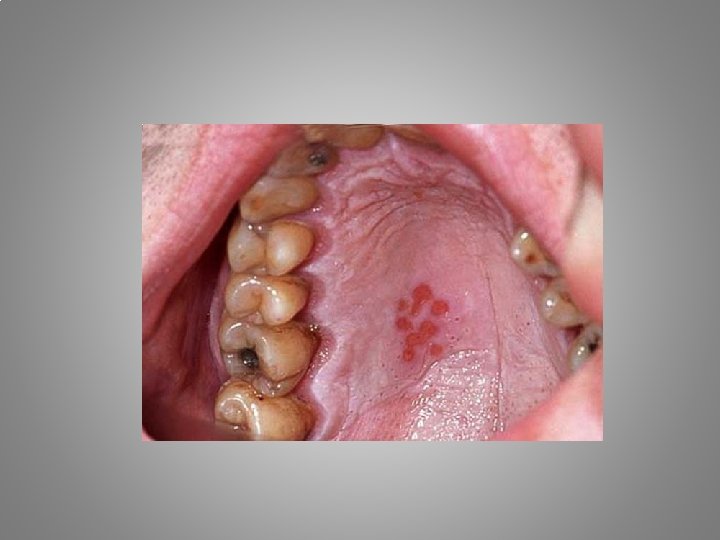

Types of orofacial pain Odontalgia : - Exposed dentin - Caries - Pulpitis - Apical periodontitis - Craced tooth sy. - Occlusal trauma - Periodontal abscessacute necrotising gingivitis - Periodontitis

• 19 years old male. A few days earlier started the pain in the submandibular area. The intraoral examination show out the edema, and erythema of the oral mucosa around 47 region. Dg. Th.